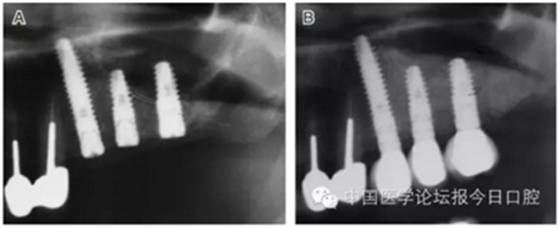

病例8 多顆種植體植入(圖10)

圖10